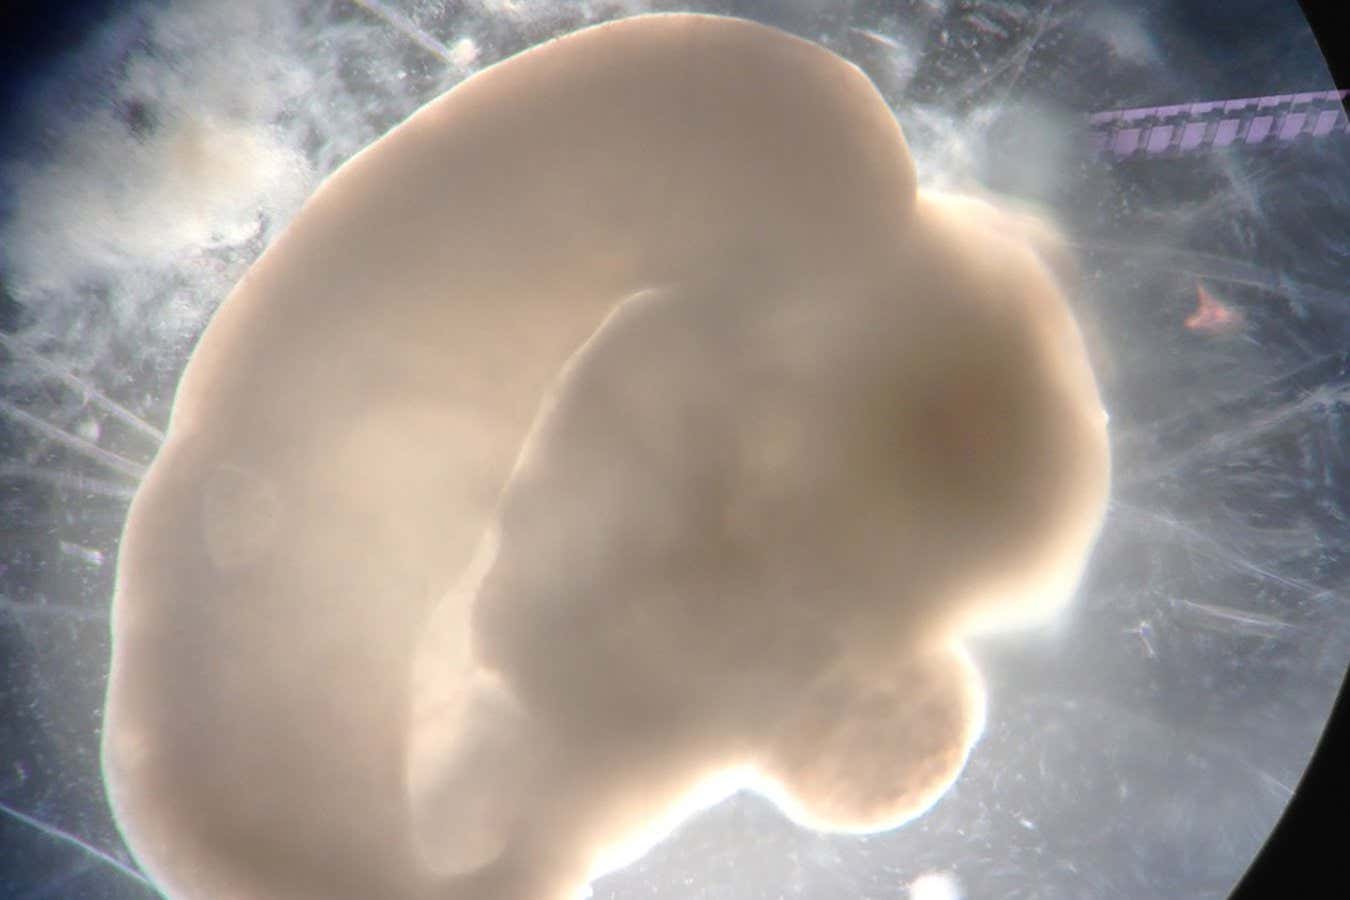

A 100-day-old brain organoid

Madeline Lancaster